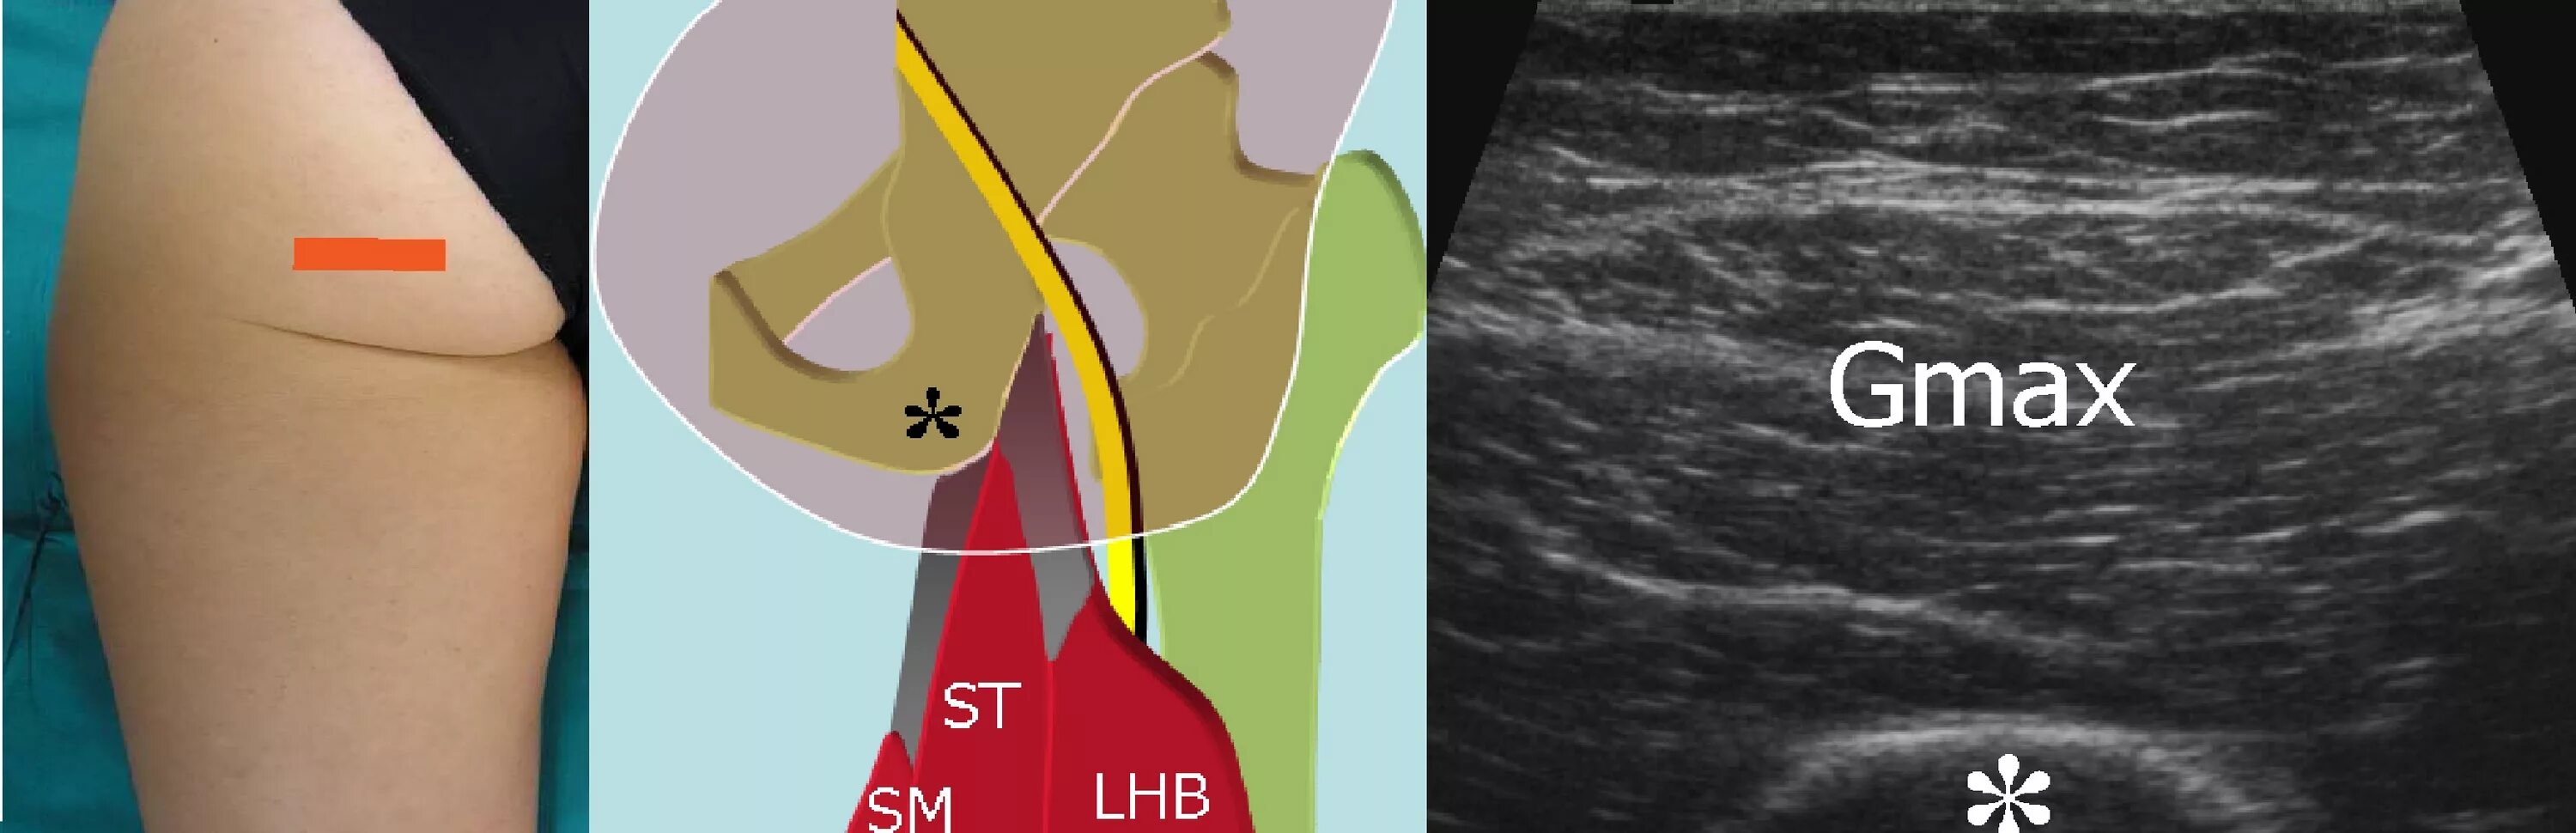

Узи тазобедренного сустава у взрослых что показывает